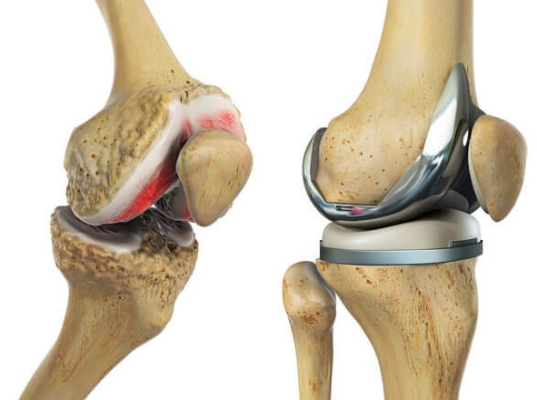

Thoái hóa khớp là bệnh khớp mạn tính có đặc điểm là nứt vỡ và mất sụn khớp cùng với những thay đổi khác của khớp, bao gồm phì đại xương (hình thành gai xương).

Phẫu thuật thay khớp gối nhân tạo là giải pháp tối ưu cuối cùng cho các bệnh nhân thoái hóa khớp gối giai đoạn nặng, điều trị nội khoa không thuyên giảm. Đây là phương pháp được ứng dụng phổ biến tại nhiều bệnh viện, trung tâm chấn thương chỉnh hình lớn trong cả nước và hiện được triển khai thường quy, hiệu quả tại Bệnh viện Đa khoa Vĩnh Đức, giúp bệnh nhân không còn đau đớn, phục hồi vận động tốt, cải thiện chất lượng cuộc sống.

Hiện tại khớp gối được đội ngũ chấn thương chỉnh hình BV Đa Khoa Vĩnh Đức sử dụng là khớp gối Medial Pivot. đây được xem là khớp kỹ thuật tiên tiến nhất và hoàn thiện nhất trong các loại khớp gối nhân tạo. Medial Pivot có cấu tạo gần giống với khớp gối tự nhiên, sở hữu nhiều ưu điểm về mặt động học, cải thiện chức năng lâm sàng, giải quyết các vấn đề về đau mặt trước gối, tăng tuổi thọ khớp, giảm nguy cơ trật khớp gối.